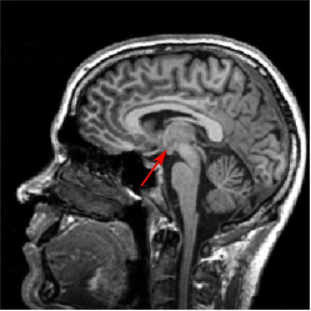

Cerebellum

- Two hemispheres, several lobes divided by fissures

- Neurons in sheets, called cortex

- Receives sensory input from spinal cord, motor info from cerebral cortex, balance info from inner ear and vestibular organs

- Primarily used for motor control, particularly in making postural adjustments and in fine-tuning movements

- Essential for the coordination, planning of movements, learning motor tasks and storing this information

Note:

Cerebellum is latin for 'little brain.'

The cerebellum is located dorsal to the brainstem.

It has two…

Neurons form cortical sheets like in the cerebral hemispheres.

Receives…

fyi: The MRI image is J. Ackman's brain from 2009!